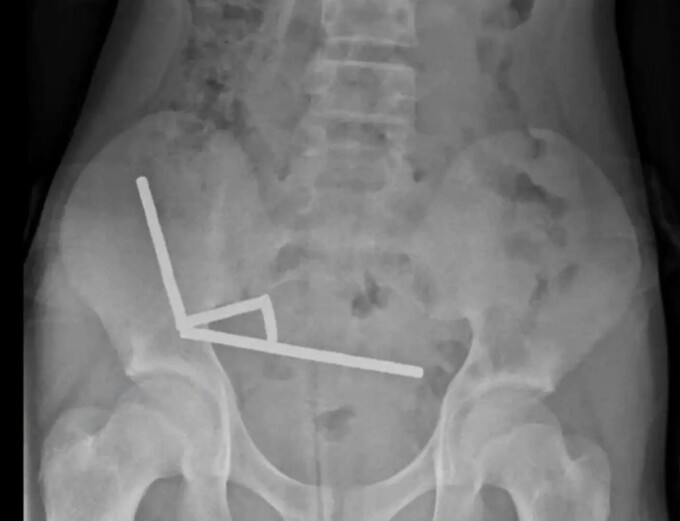

Radiografiile au arătat patru lanțuri de magneți blocate în diferite secțiuni ale intestinelor, care se atrăgeau reciproc și blocau fluxul sanguin către țesutul din apropiere. Medicii au explicat că această presiune a provocat multiple zone de necroză – adică zone de mucoasă intestinală moartă – ceea ce a necesitat o operație de urgență.